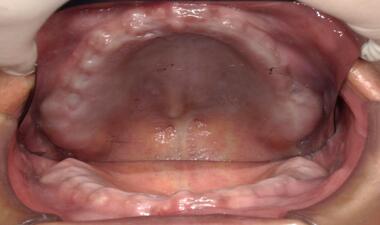

術中

上顎缺牙,植入六顆植體